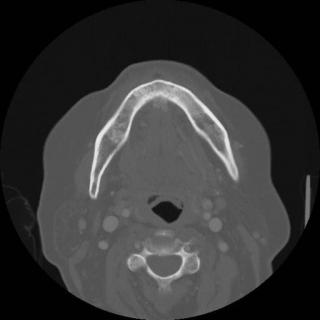

КТ зубов и челюсти является приоритетной формой диагностики костей, поскольку в костных тканях рентгеновские лучи задерживаются в большем объеме. Если перед врачом стоит диагностическая задача оценить структуру зубов и челюсти, он выберет рентгенологические метод диагностики. КТ челюсти хорошо покажет травматические повреждения костей лица, остеонекроз, остеоартроз, остеоартрит, остеомиелит. МРТ челюсти фокусируется на качественной визуализации мягких тканей и состояния височно-нижнечелюстного сустава. С ее помощью можно хорошо оценить воспаления суставных тканей, дисфункции ВНЧС, новообразования. Поскольку в костных структурах содержится мало воды, добиться хорошего резонанса в них сложно, поэтому кости на МРТ снимках отображаются с наименьшей точностью.

КТ челюсти - это обследование на мультиспиральном компьютерном томографе (МСКТ). Задача этого сканирования в отображении состояния верхней и нижней челюсти, зубов, гайморовых пазух, челюстных суставов и прилегающих мягких тканей.